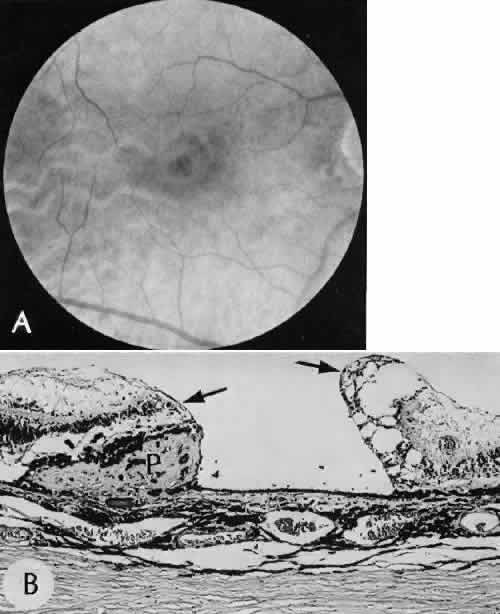

Cyclocryotherapy, cyclodiathermy (Fig. 20), and therapeutic ultrasonography apply energy directly to the pars plicata and cause lysis of the ciliary muscle and occlusion of the vascular supply, leading to extensive necrosis and scarring. Pressure lowering is accomplished by a reduction of aqueous production. Heat applied to the sclera may cause necrosis and localized scleral thinning. Cold applied to the sclera, unless extreme, does not cause any clinical or histologic changes.

Fig. 20. Cyclodiathermy treatment of the ciliary body to control glaucoma. A. Gross photograph illustrates extensive areas of depigmentation mainly in the region of the pars plana (arrows) rather than the pars plicata. B. Light micrograph of the region of the pars plana illustrates an extensive area of tissue degeneration of the pars plana (between arrows) in the late postoperative course. C. Light micrograph of the destructive effects of cyclocryotherapy also in the region of the pars plana and pars plicata. The ciliary epithelium in the early postoperative period is necrotic and cystic. (Hematoxin-eosin stain; A, × 8; B, × 16.)